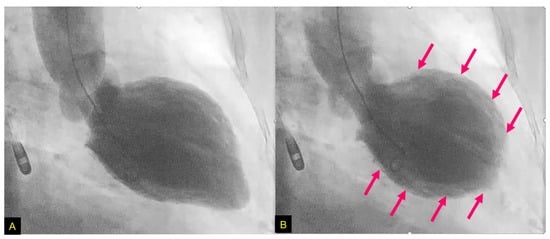

- Nagai, M.; Kobayashi, Y.; Kobatake, H.; Dote, K.; Kato, M.; Oda, N.; Kunita, E.; Kagawa, E.; Yamane, A.; Osawa, A.; et al. Happy heart syndrome: A case of Takotsubo syndrome with left internal carotid artery occlusion. Clin. Auton. Res. 2020, 30, 347–350. [Google Scholar] [CrossRef]

- Osawa, A.; Nagai, M.; Dote, K.; Kato, M.; Oda, N.; Kunita, E.; Kagawa, E.; Yamane, A.; Kobatake, H.; Shiota, H.; et al. A mid-ventricular variant of Takotsubo syndrome: Was it triggered by insular cortex damage? ESC Heart Fail. 2021, 8, 3408–3412. [Google Scholar] [CrossRef]